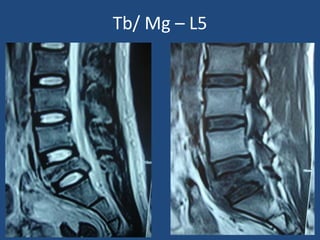

Tb/ Mg – L5 25/M

Tb/ Mg – L5

Tb/ Mg L5